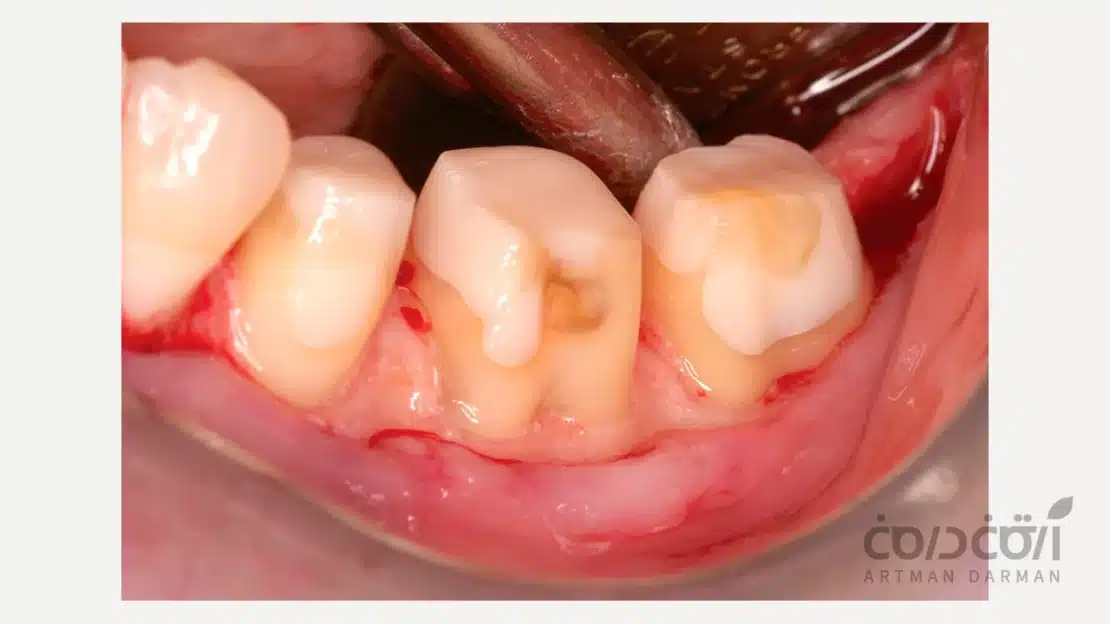

برای درک صحیح بیلداپ دندان، ابتدا باید ذهنیت خود را از واژه پر کردن دندان خالی کنید. پر کردن دندان معمولا برای حفره های کوچک و متوسطی انجام می شود که دیواره های دندان هنوز قادر به تحمل فشار هستند. اما زمانی که تخریب دندان زیاد باشد، به گونه ای که یک یا چند دیواره اصلی یا کاسپ ها (برجستگی های تاج دندان) از بین رفته باشند دیگر یک ترمیم ساده پاسخگو نیست.

بیلداپ کامپوزیت، در واقع فرآیند بازسازی تاج دندان است. در این روش، دندانپزشک با استفاده از مواد کامپوزیتی پیشرفته و بهره گیری از تکنیک های لایه گذاری، آناتومی از دست رفته دندان را بازسازی می کند.

در این روش هدف تنها پر کردن یک حفره نیست؛ بلکه هدف، بازگرداندن فرم صحیح دندان، ایجاد نقاط تماس مناسب با دندان های مجاور و از همه مهم تر، بازگرداندن عملکرد دندان برای جویدن است. در بیلداپ، مواد ترمیمی با استفاده از سیستمهای باندینگ پیشرفته به بافت دندان متصل می شوند و یک ساختار یکپارچه را ایجاد می کنند که می تواند نیروهای وارده را به صورت متعادل در طول ریشه پخش کند.